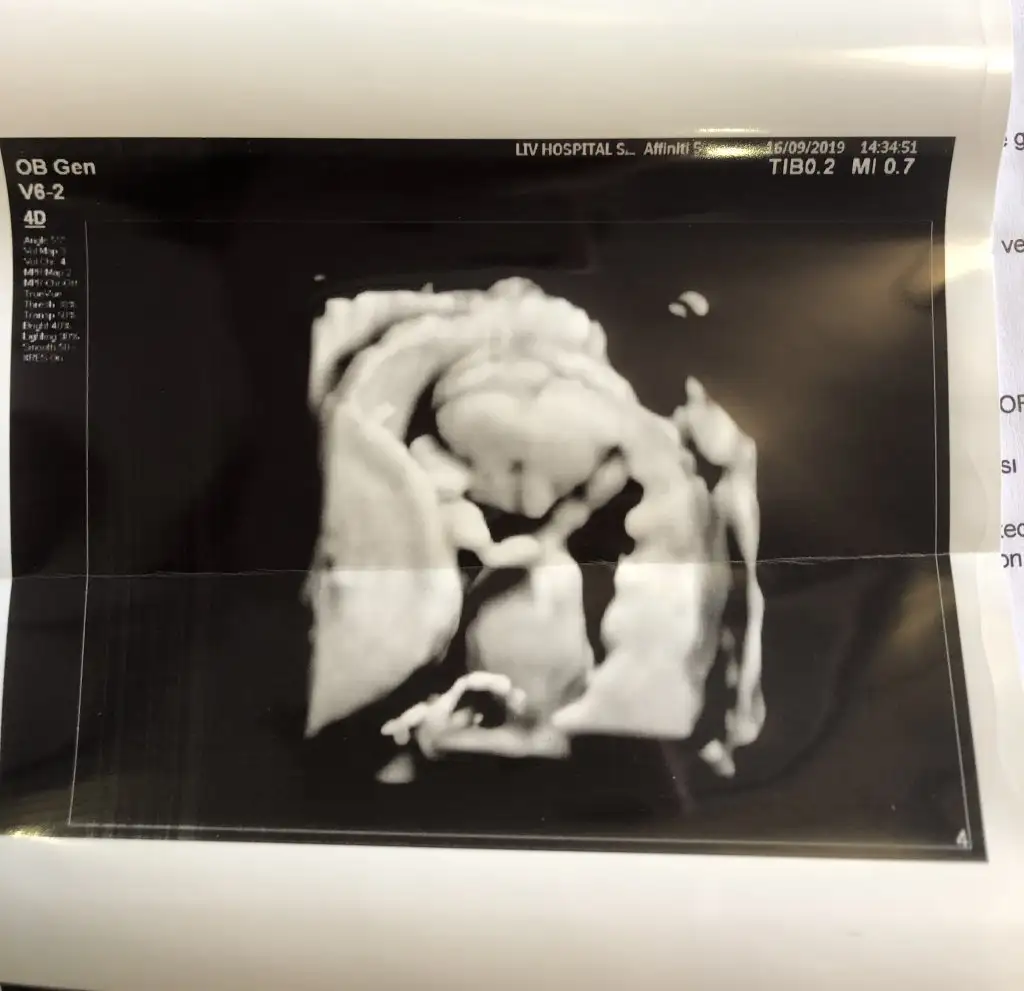

Benim oğlumda bu şekil durmuştu , göbek bağı sağa doğru sanki ama tamamen tahmin tabi . Sağlıklı olur inşallah canimTwiekkürler canım yprumun için neye bakarak erkek dedin acaba kafa yapısı nub falan mı ben hiç yorumlayamıyorum da ondan sordum

İnşallah canım teşekkür ederimBenim oğlumda bu şekil durmuştu , göbek bağı sağa doğru sanki ama tamamen tahmin tabi . Sağlıklı olur inşallah canim

Başka bir postta paylaşmıştım erkek tahmin ettiniz bakalım hangi teori tutacak :)))Sola yakın vajinal usg buna göre kız ,ama siz 11 yada 12 hafta nub için usg paylaşın

Gönlünüzdeki saglıkla nasip etsin rabbim ilk bebişmiBaşka bir postta paylaşmıştım erkek tahmin ettiniz bakalım hangi teori tutacak :)))

İlk kez kız dendi acayip heyecanlandım ama ben de erkek hissediyorum bakalım sonuç ne olacak :)